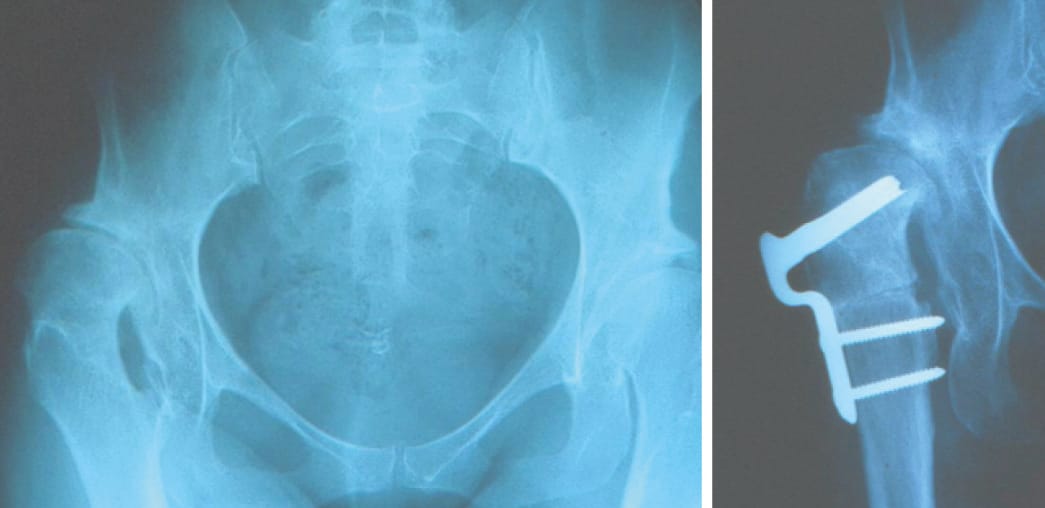

Femoral osteotomy

Historically in cases of DDH associated with femoral valgus, a femoral varus osteotomy may have been offered, however this can complicate a subsequent THA, especially if it leads to translation or an issue with rotation. With the advent of acetabular reorientation strategies, femoral osteotomy finds its indication in combination with acetabular reorientation due to fovea alta (reducing the cartilaginous contact surface), poor congruence or a tilt defect, or as a salvage strategy (Figure 9). Thorough planning is required and fixation can be achieved with a locked plate or blade plate, with the advantage of the latter being that they are low-cost and the fixed angle makes planning straightforward.